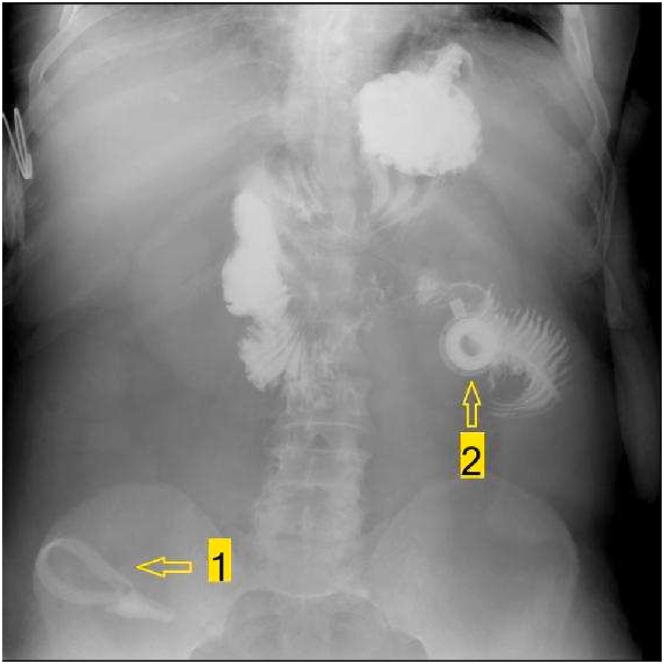

腹腔镜可调节胃束带术(LAGB)是减肥手术中一种已获批准的术式。然而,已有因束带侵蚀导致严重并发症的报道。胃束带侵入胃壁并迁移至空肠引起肠梗阻和穿孔的报道较少。病例介绍:一名56岁男性在接受LAGB手术后10年因右下腹痛入院。术中发现胃束带侵蚀胃壁并下移至空肠,导致肠梗阻和空肠穿孔。结论:胃束带手术后患者应定期接受门诊胃镜随访,以预防严重并发症。